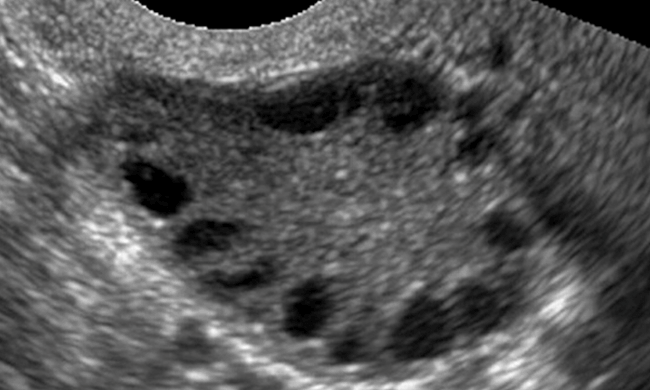

“Polycystic Ovary” can be a normal finding if there are no weight issue, abnormal menstruation or infertility. If such issues are present, then polycystic ovaries may indicate the presence of a metabolic condition called Polycystic Ovarian Syndrome. (PCOS)